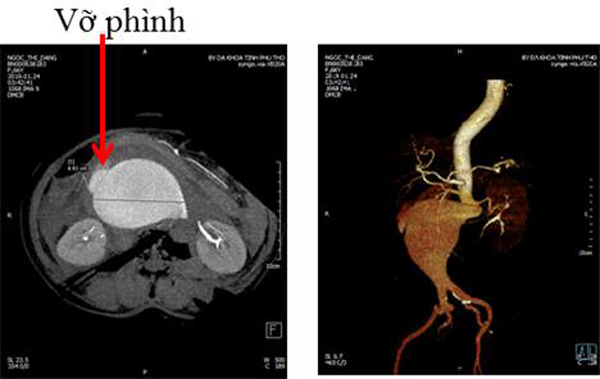

Ngay sau khi vào viện, bệnh nhân được duy trì thuốc vận mạch. Hình ảnh chụp cắt lớp cho thấy khối phình động mạch chủ bụng dưới động mạch thận đường kính hơn 9cm, đang bắt đầu chảy máu và tụ máu lớn sau phúc mạc.

| Mạch chủ bụng bệnh nhân phình to |